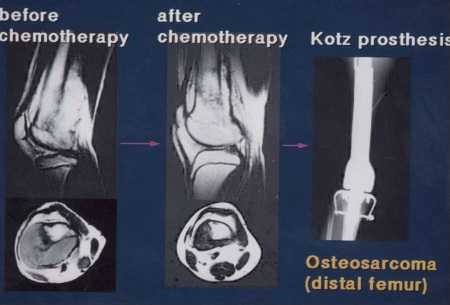

四肢発生の悪性骨軟部腫瘍に対する手術法として,以前はもっぱら切断が行われていましたが,現在では制癌剤や放射線による局所コントロールの向上,画像診断の発達による腫瘍進展範囲の的確な把握,手術法の発達などにより,ほとんどの症例で患肢温存手術が可能になっています。例えば,私が過去10年間に手術を行った悪性軟部腫瘍の患者さんのうち,患肢温存例は実に全体の96%にも及んでいます。しかも,患肢温存手術を行ったからといって,切断よりも生命的予後が悪くなることはありません。